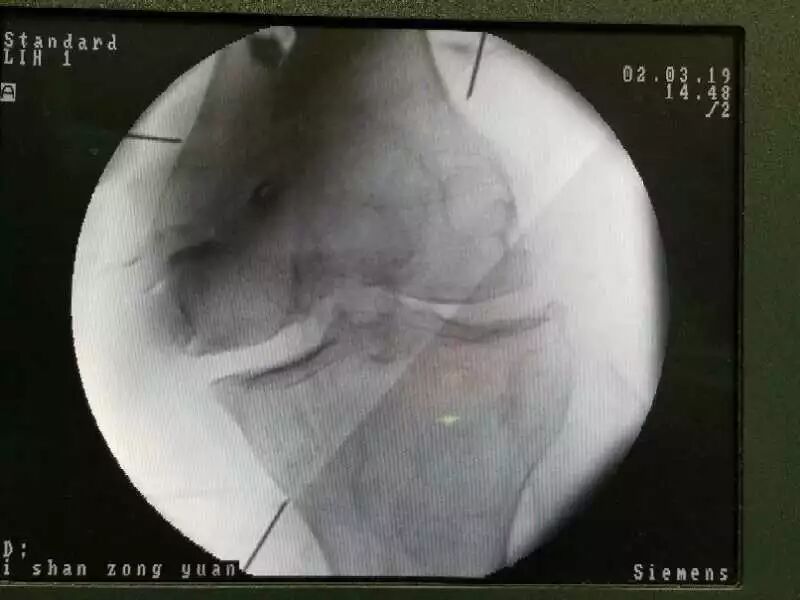

4、C-臂引导下椎间孔镜技术,对于腰椎间盘的较大突出术后立竿见影,非常令人满意。

可视———影像学和电生理引导下的介入治疗,即在超声、X线透视或CT引导下进行